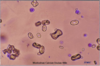

Ammonium Biurate Crystals

Bilirubin Crystals

Calcium Carbonate

Calcium Oxalate Dihydrate

Calcium Oxalate Monohydrate

Cholesterol Crystal

Hippuric Acid

Leucine Crystal

Struvite Crystals

Tyrosine

Uric Acid Crystals